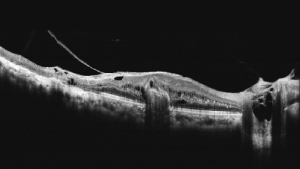

Чудова якість ОКТ-зображень з усередненням 100 зображень

Mocean 4000 робить 100 зображень менш ніж за одну секунду і об'єднує їх разом для створення зображення високої чіткості з мінімізованим шумом зернистості

Осьова оптична роздільна здатність 5 мкм (цифрова - 3 мкм)

ОКТ-зображення з високою роздільною здатністю виявляє приховані патологічні зміни